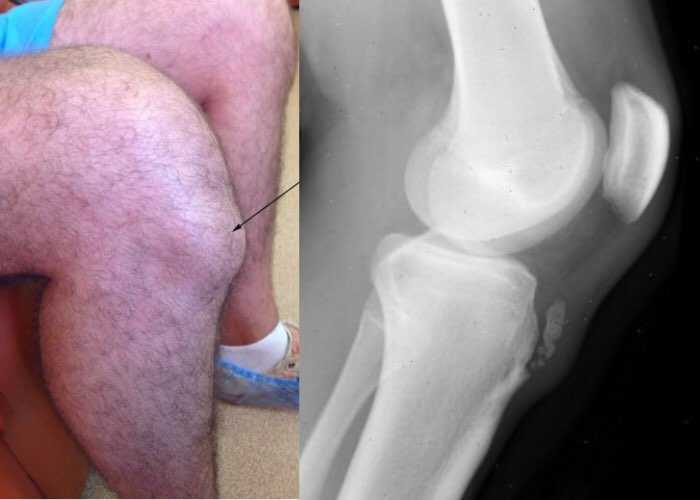

Повреждение коленной чашечки

Коленная чашечка или надколенник часто травмируется на фоне падения на внешнюю поверхность сочленения. Перелом часто отмечается у начинающих спортсменов, например, во время приседания с нагрузкой.

Главной причиной является нарушение техники приседания. Явление сопровождается интенсивной, острой болью, ярко выраженной припухлостью, образованием подкожной гематомой. Утрачивается возможность удерживать поднятую конечность.

• рентгенография – снимки показывают наличие травмы, образования остеофитов;